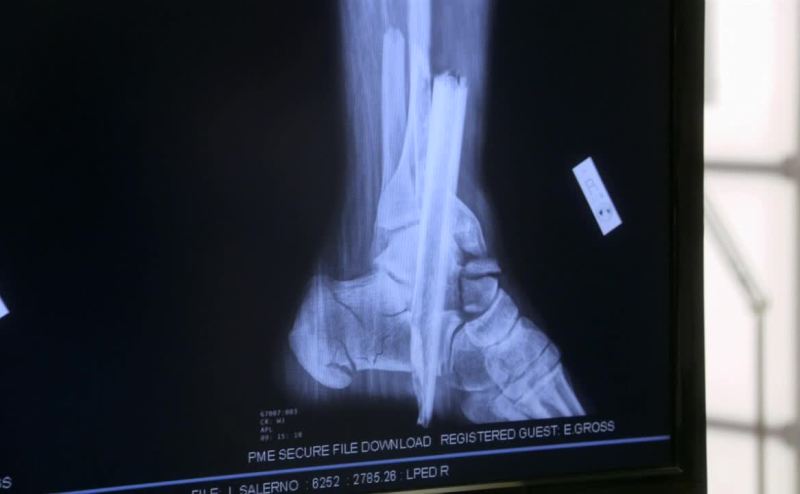

The tibia bones were driven into the bottom of the feet.

The heel bones were fractured bilaterally.

- The impact was vertical. - Vertical?

Yeah, you see it with jumpers all the time.